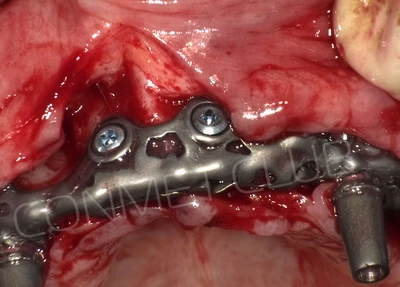

Если все проектирование прошло идеально, то сама операция будет выглядеть следующим образом:

Сама же операция длиться 20-50 минут в зависимости от количества утраченных зубов. В процессе этой операции, после проведенной местной анестезии, делается разрез на слизистой, она приподнимается и субпериостальный имплантат укладывается на кость. После этого рана фиксируется несколькими швами и все! Через 10-14 дней мягкие ткани срастаются и надкостница надежно удерживает имплантат на месте. Нет необходимости ждать несколько месяцев, как это бывает в случае с внутрикостными винтовыми имплантатами.